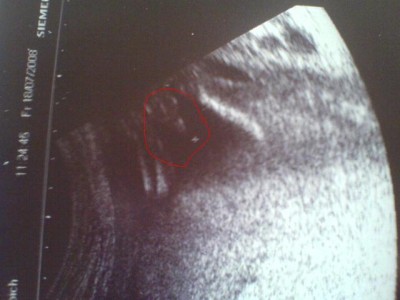

So nun mal kurz zu uns, also heute kam ein sehr eindeutiger beweiß zu dem Thema geschlecht. Das konnte man echt nicht über sehen. Überzeugt euch von dem Foto gleich selber. Hatten ja schon den verdacht aber nun hat es sich entgültig bestätigt. Baby geht es aber soweit prima, Organe alle in Ordnung und größe auch zeitgerecht. Ist jetzt zwischen 20 und 22cm groß und hilfe der Kopf schon bei 12cm. Himmel wird wird angst und bang wenn ich an Dezember denken. Aber das ist noch soooo weit hin bist dahin. Zu dem anderen Thema, beim Togo war heute ne Wehe die etwas zu dolle ausgeschlagen hat, und heute nacht hatte ich was Blut im Slip. Ist aber wieder weg. Nur die Wehen eben nciht. Es sind zwar nur Übungswehen die dazu gehören, aber da sie auch nciht weniger werden im Moment und ab und an ziemlich ausschlagen, wird jetzt jeder Tag etwas kritischer wo sie nicht weggehen. Sprich kann sonst echt ersnt werden für den kleinen und in die Hose gehen. Also wir haben es ab und an nun mit richtigen WEhen zu tun. Das heißt absolute Schonung noch mehr. Nur zum Kloh und gut ist, damit da nicht noch zusätzlich Druck drauf kommt und doch der muttermund auf geht. Etwas weicher war er heute nämlich schon. Aber der Gebärmutterhals ist absolut ok von der Länge.

@Despo, das ist ja mal ne "Nabelschnur" oder

na depo wenn das nicht eindeutig ist fress ich nen besen...so ne schöne aufnahme...habt ihr schon nen namen...wünsche ir noch viele schöne ss-tag..lg jule

Despo: Süüüß...und wahrhaftig eindeutig....das ist nicht zu übersehen

@Despo: Jo das ist wohl eindeutig.